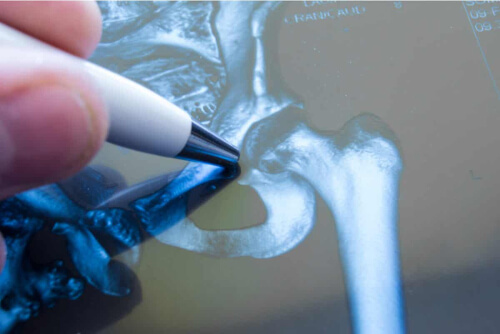

Zanim wyjaśnimy, czym jest uszkodzenie obrąbka panewki stawu biodrowego, warto najpierw się przyjrzeć, jak wygląda ten staw. Biodro to staw kulisty. Panewka natomiast to wgłębienie w kości biodrowej, do którego pasuje górna część kości udowej.

Ta część, która ma kształt kuli, nosi nazwę głowy kości udowej. Na krawędzi zagłębienia panewki znajduje się pierścień tkanki chrzęstnej, czyli obrąbek. Jak wskazuje artykuł w Sports Medicine Oregon, ta struktura zwiększa stabilność stawu.

Kiedy dochodzi do uszkodzenia obrąbka panewki stawu biodrowego, w zasadzie chodzi więc o uszkodzenie tkanki chrzęstnej. W związku z tym panewka przestaje prawidłowo pełnić swoją funkcję. Jedną z konsekwencji jest utrata części podparcia głowy kości udowej.

Jednak zwykle wykonuje się pewne badania uzupełniające, aby wykluczyć inne zmiany. Do najczęściej stosowanych w tym wypadku należy radiografia. Za pomocą obrazu można zaobserwować, czy nie ma złamania lub nieprawidłowości w budowie kości. Jest to szczególnie przydatne, jeśli doszło do urazu.

Ale miękkich tkanek ciała nie można zobaczyć na zdjęciu rentgenowskim. Z tego powodu czasami stosuje się również rezonans magnetyczny.